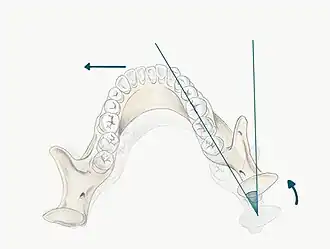

6) RCP

The patient may be guided into CR using one of the follow methods;

- Bimanual manipulation- manipulating the patient's condyles so they are in CR

- The operator should lightly rest their fingers along the inferior border of the mandible and their thumbs should lie lightly on the anterior aspect of the chin

- When the patient is relaxed place light downward pressure on the chin and light upward pressure under the angle of the mandible

- Deprogramme the jaw by guiding the opening and closing of the jaw and once the patient is relaxed, ask them to close gently and stop when they feel teeth first contacting

- Chin point guidance- one hand is used to apply pressure to the chin guiding the chin posteriorly with some force

In some patients it may be difficult to guide the mandible into CR, for example in those with muscle tension, muscle splinting, occlusal disharmony or parafunctional habit. For these patients a Lucia Jig or deprogramming appliance can be constructed at chair-side.

Mark RCP tooth contacts using articulating paper, note the teeth which are contacting and identify whether this RCP position is causing problems related to the occlusion. For example if there is a heavy contact or interference in RCP this may be the cause of occlusal disturbance. It is important to be able to guide the patient into RCP, as a registration may need to be taken in this position particularly if the occlusion is being reorganised, the OVD is being changed or even just for diagnostic and treatment planning purposes.